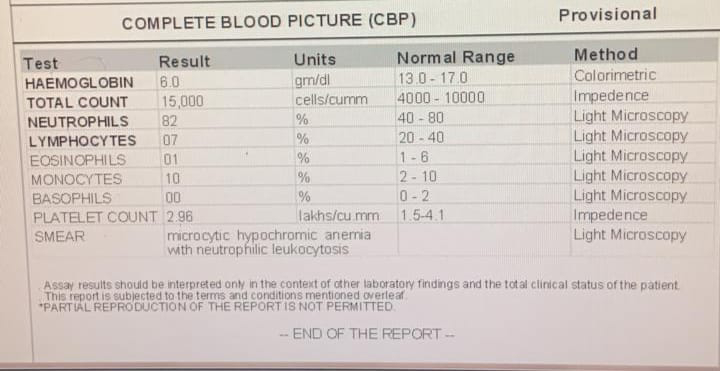

[8/5, 10:10 AM] +pajr_doctor: Sending some routines required sir PAC sir

[8/5, 12:42 PM] PaJR PHR Moderator: Even his previous OT was under spinal following which he went into delirium?

[8/5, 12:58 PM] pajr_doctor: Yes sir

[8/5, 12:58 PM] +pajr_doctor: Now they are doing it under local anesthesia

[8/5, 2:00 PM] pajr_doctor : Implant removal done under LA by doctor sir